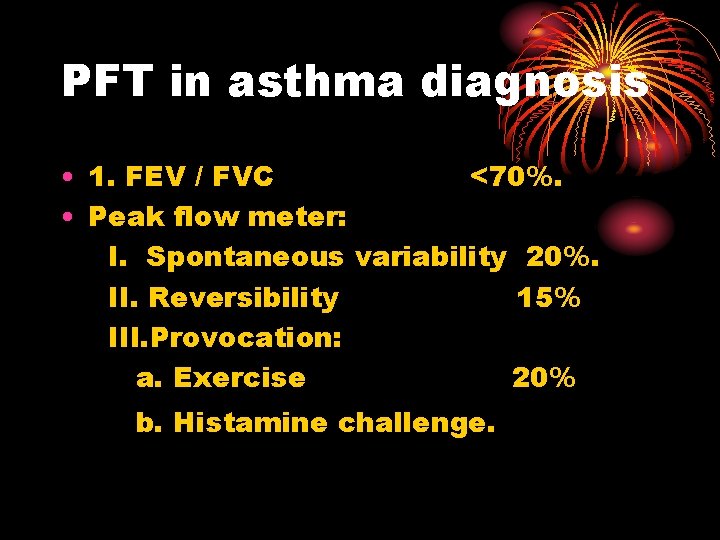

PFT in asthma diagnosis • 1. FEV / FVC <70%. • Peak flow meter: I. Spontaneous variability 20%. II. Reversibility 15% III. Provocation: a. Exercise 20% b. Histamine challenge.